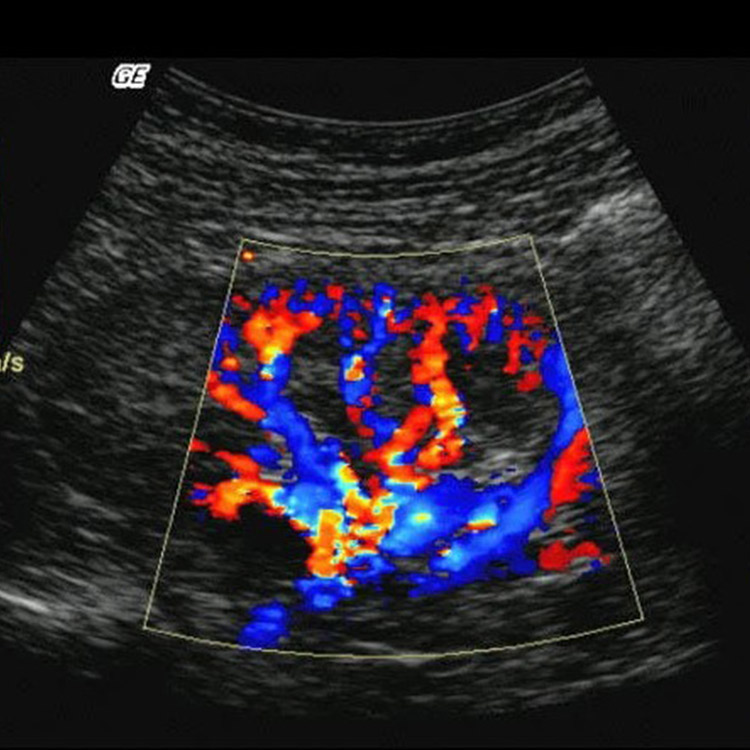

Modern radyolojik görüntüleme, hastalıkların net ve güvenilir şekilde değerlendirilmesini sağlar. Doğru tanı; gereksiz işlemlerin önüne geçer, tedavi sürecini hızlandırır ve hastaya güven verir.

Yüksek çözünürlüklü cihazlar ve güncel radyoloji teknikleri sayesinde daha ayrıntılı görüntüler elde edilir, tanısal doğruluk en üst seviyeye taşınır.